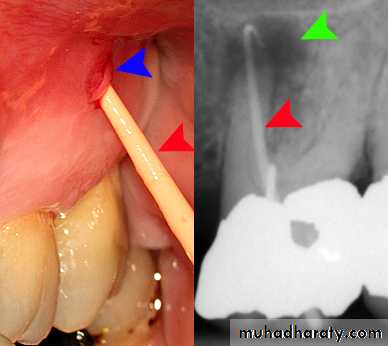

Facial cellulitis occurs when an infected root canal system

develops a periapical abscess (usually a secondary acute

apical abscess, although it could be a primary acute apical

abscess) and the infection spreads between the fascial planes of the muscles of the face, head, and/or neck (It is a spreading infection and it can be superficial or deep. In either case, it can be life-threatening if the resultant swelling restricts the airway. Patients with facial cellulitis require immediate and aggressive treatment—that is, not just oral antibiotic therapy but active dental treatment to remove the source of the bacteria. They often require hospitalisation

and even management in an intensive care unit to protect the airway and provide life support in severe cases.

Typical symptoms—facial swelling that is increasing in size—often rapidly; the swelling has had rapid onset (e.g., hours); the patient has considerable pain and discomfort; the pain has only been present for a short time (usually less than 24 hours); there is pain to biting or pressure on the tooth; no thermal sensitivity; the patient has fever and feels unwell.

Clinical findings—facial swelling is evident; may be caries, a restoration breaking down or a crack; very tender to percussion; no response to pulp sensibility tests; tender to palpation; the patient has fever, malaise and lymphadenopathy; severe cases may have airway involvement; typically also have localized signs of a secondary acute apical abscess as the abscess usually occurs before the infection spreads to become facial cellulitis.

Radiographic findings—caries may be seen if extensive enough;

there is a periapical radiolucency present indicates chronic apical

periodontitis has been present for some time before the abscess and facial cellulitis

developed; some cases may have evidence of previous endodontic treatment; occasionally may see a radiolucency within the tooth root indicating internal inflammatory resorption.

Key findings for diagnosis—there is facial swelling of rapid onset, the swelling is spreading, the patient has fever, feels unwell, has a periapical radiolucency, and pain with pressure and percussion.